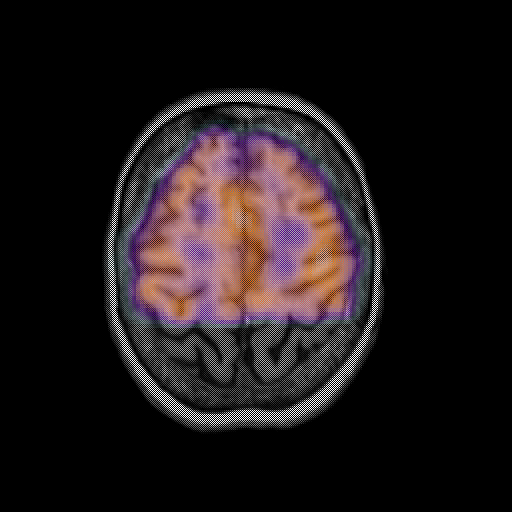

overlay: Slice 41

Slice 41